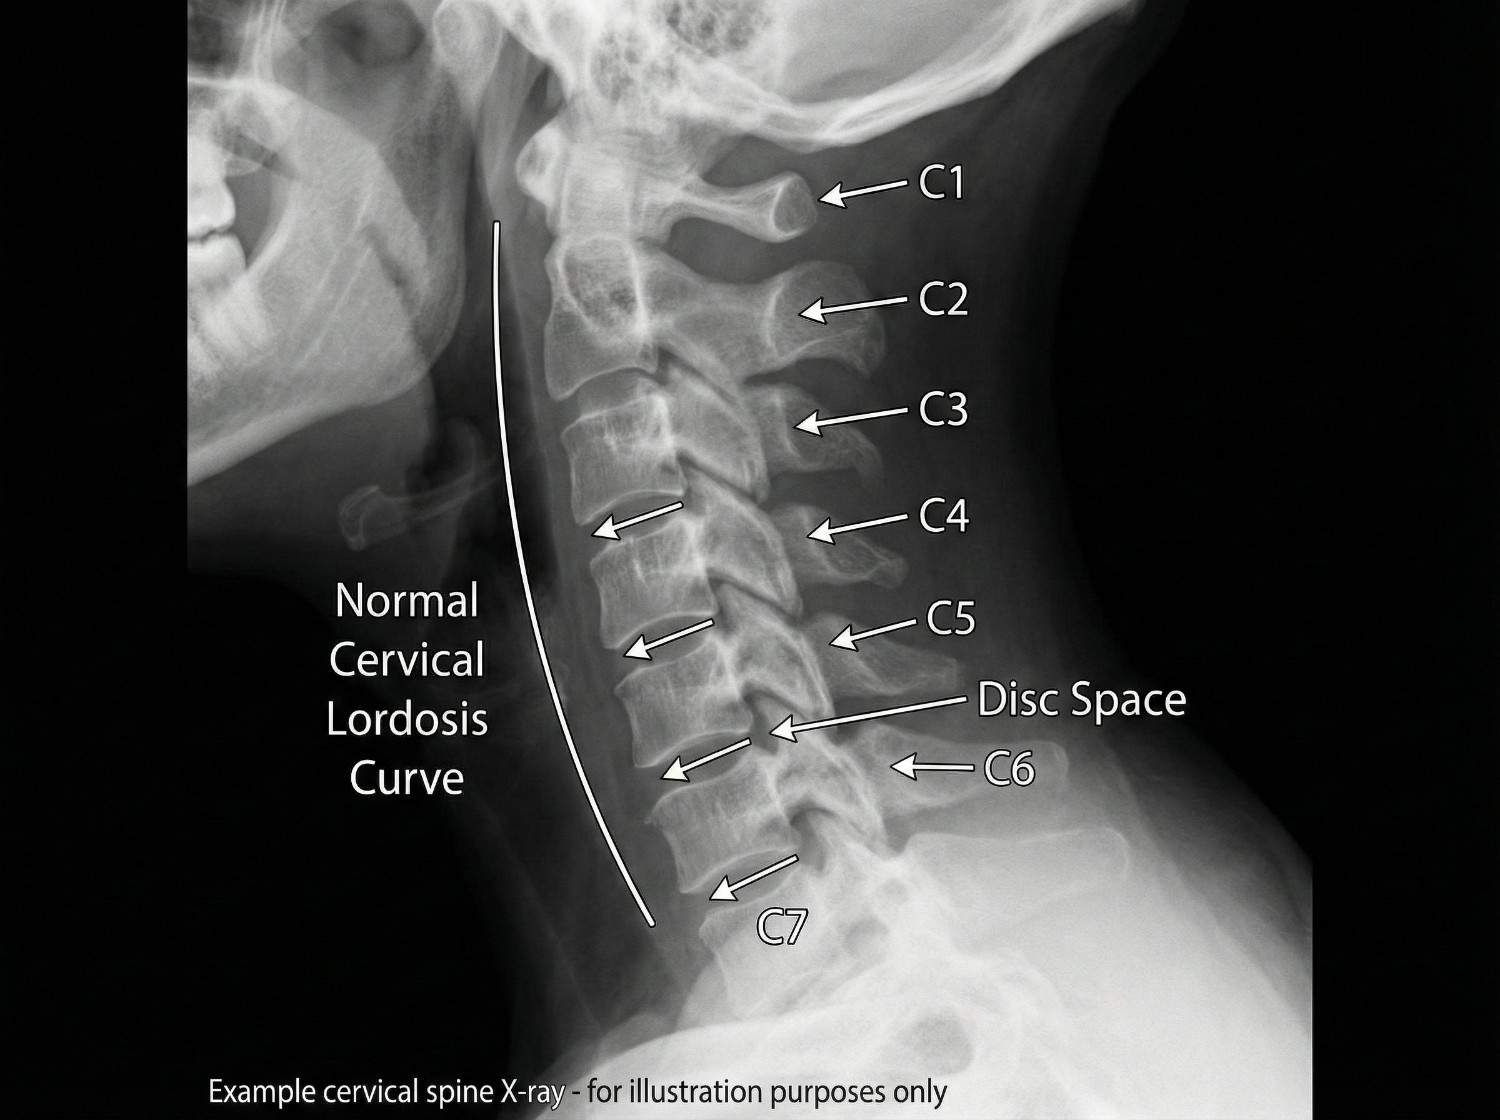

Whiplash is a complex soft tissue injury involving the cervical spine's intricate network of seven vertebrae (C1-C7), intervertebral discs, facet joints, muscles, ligaments, and nerve roots. The injury mechanism typically involves a hyperextension-hyperflexion sequence: during rear-end collisions, the torso is thrust forward by the seatback while the head momentarily remains stationary due to inertia. This creates an S-shaped curve in the cervical spine, straining the anterior longitudinal ligament and anterior neck muscles. Milliseconds later, the head snaps forward into hyperflexion, overstretching the posterior ligaments, facet joint capsules, and paraspinal muscles.

The forces involved can exceed 5G of acceleration, causing microscopic tears in muscle fibers, ligament strains, facet joint capsule injuries, and in severe cases, intervertebral disc damage or nerve root compression. The C5-C6 and C6-C7 spinal segments bear the greatest stress due to their location at the cervical spine's mobile center. Research published in the Journal of Orthopaedic & Sports Physical Therapy demonstrates that even low-speed collisions (5-10 mph) can generate sufficient force to cause whiplash, as the sudden acceleration-deceleration exceeds the neck's protective muscle contraction response time.

Physical examination assesses multiple cervical spine parameters: active and passive range of motion measurement in six planes (flexion, extension, right/left rotation, right/left lateral flexion) using inclinometry or goniometry for objective documentation. We palpate all cervical vertebrae (C1-C7) for point tenderness, assess paraspinal muscle tone and spasm severity, and examine facet joint tenderness with pressure over the lateral masses. Neurological testing includes deep tendon reflexes (biceps C5, brachioradialis C6, triceps C7), sensory examination in all dermatomes, and manual muscle testing for myotomal weakness. Spurling's test (cervical compression with rotation and extension) reproduces radicular symptoms if nerve root compression exists.

Imaging studies are selected based on clinical presentation: Standard cervical X-rays (AP, lateral, open-mouth odontoid) are initial studies to rule out fractures, assess vertebral alignment, measure cervical lordosis, and evaluate disc space heights. While X-rays don't visualize soft tissues, they identify bony abnormalities and instability. MRI (magnetic resonance imaging) is the gold standard for soft tissue evaluation, revealing disc herniations, ligament tears (especially the alar and transverse ligaments at C1-C2), facet joint effusions indicating capsule injury, spinal cord signal changes, and nerve root compression. We order MRI when neurological symptoms exist, severe pain persists beyond 4-6 weeks, or clinical examination suggests disc or ligament injury.